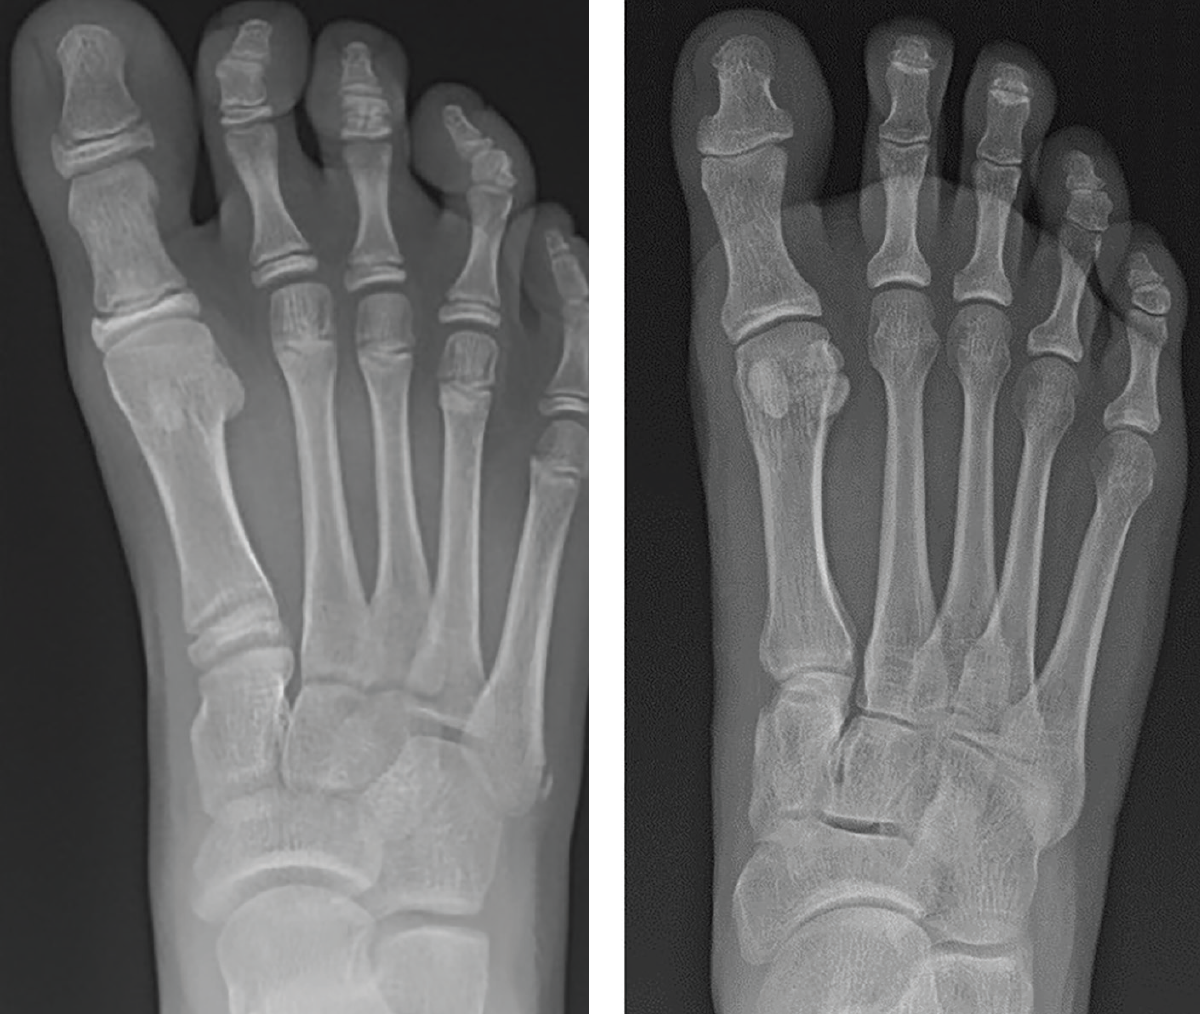

The literature traditionally presents idiopathic hallux varus as a rare clinical entity.1,2 Unfortunately, there is currently a paucity of literature related to idiopathic hallux varus, with iatrogenic hallux varus appearing more frequently in publications. Over 30 years of tracking clinical and radiographic cases, I have amassed encounters of over 700 cases of idiopathic hallux varus. We have catalogued 153 cases within our radiographic database at Ft. Leonard Wood in the last 5 years. Many would think hallux varus to be a severe deformity (see left two images below), but in reality, most of what we all tend to see is less extreme (see right image below).

Within our database, to date, we have not seen a negative intermetatarsal angle in any idiopathic hallux varus case. We routinely see normal intermetatarsal angles and often see some greater than 10 degrees. We routinely see normal sesamoid positions. In our experience, the deformity is almost always a negative PASA deformity. For iatrogenic, it seems like everyone focuses on the sesamoids, but there can be multiple permutations of sesamoid shape, position, or even lack of sesamoids. I then wondered if metatarsal length played a role, but my archives show multiple cases with short and long first metatarsals (see images below). All have the same etiology, incongruent first MTPJ, and negative PASA.